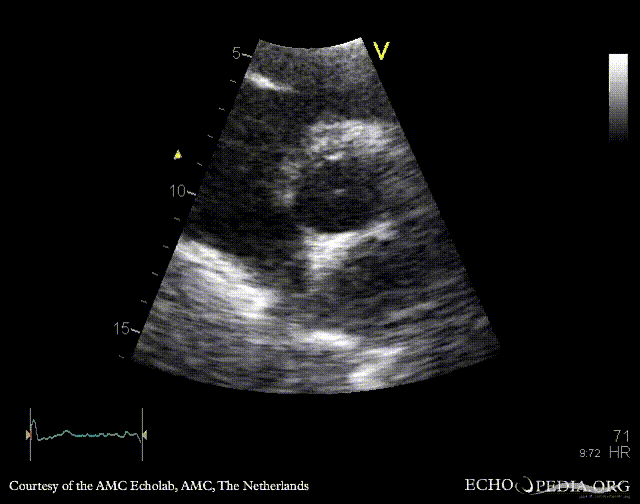

E00418.gif E00419.gif

PLAX: Color Doppler, moderate aortic regurgitation PSAX